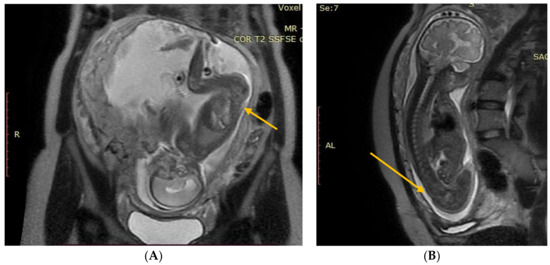

The next follow-up test, a fontanelle ultrasound, was performed every 5–7 days of neonatal life to assess the size of the cerebral ventricles and location of the posterior fossa structures. The dynamics of hydrocephalus progression was assessed based on the measurements of the lateral ventricular size (anterior horns and stem) and increased resistance index of the anterior cerebral artery (RI ACA) on follow-up ultrasound, as well as the measurements of the head circumference and palpable tension of the anterior fontanelle. The measurements were then used to determine the need to place Ventriculo-Peritoneal shunt (V-P-shunt) if the anterior horn and lateral ventricular size exceeded the 90th percentile on the pediatric ultrasound scale, and continued rising, RI ACA was >0.75, and increased tension of the anterior fontanelle failed to resolve [7,8] (Figure 3 and Figure 4).

Figure 3. Normal appearance and size of the ventricles on fontanelle ultrasound.